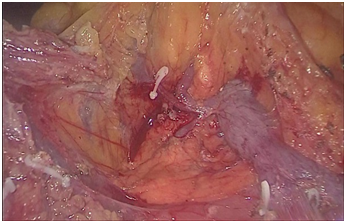

手术图片

腹腔镜胆总管切开取石+T型管引流术

复杂性肝内胆管结石术中胆道镜联合激光碎石术